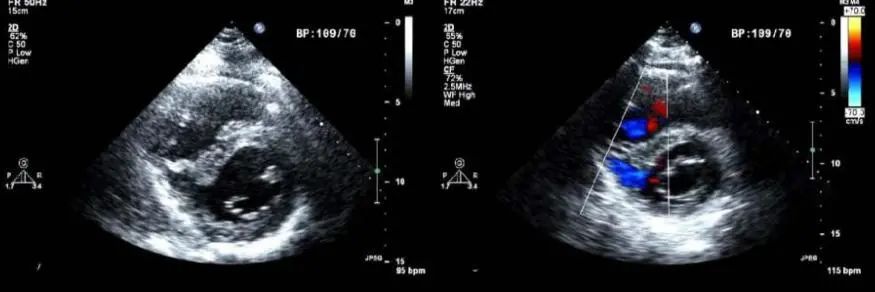

此培训为MAYO诊所推出的心内科fellow系列培训之一,主要目的是能够使大家学习到AMI以后心脏机械并发症的识别和诊断,还有ACS的非心脏的并发症的表现,以及临床中存在与ACS临床上有相似之处的非心脏疾病。 急性心肌梗死后出现的并发症,分为心脏性和非心脏性的,心脏并发症又包括心电学方面的并发症以及机械并发症,非心脏性并发症包括血栓栓塞和出血,还可能出现与心包相关的并发症。 心脏机械并发症包括就是破裂性和非破裂性的2类,破裂性并发症包括游离壁破裂、室间隔穿孔和乳头肌断裂,其中游离壁破裂既可能是直接的穿孔,也可以是亚急性破裂形成假性动脉瘤这样包容性的破裂。而非破裂性机械并发症包括严重的左室心力衰竭,右室梗塞,左室壁动脉瘤以及缺血性二尖瓣反流。 从根本上来说,这些严重并发症的发生都与心脏的泵功能衰竭有关,泵功能的衰竭造成了血流动力学不稳定以及基线的电不稳定性。 第一节:非破裂性机械并发症 非破裂性机械并发症,即严重的左室心力衰竭——心源性休克,右室梗塞,左室壁动脉瘤以及缺血性二尖瓣反流。 1、 心源性休克:在心梗发生时,发生心源性休克的主要原因就是大面积的心肌梗死,那么如果要导致心脏泵功能衰竭,左室心肌质量至少要损失40%以上。其他导致心源性休克的原因还有右室梗塞、心脏破裂以及快速和缓慢性心律失常。 2、 右室梗塞:也是导致心源性休克发生的重要原因。在下壁心梗的患者中,大概有33%的患者同时也发生右室梗死,这种情况多见于RCA近端闭塞,与高死亡风险相关。在所有下壁STEMI者中都要考虑是否同时存在RV梗塞,心电图V1和RV4导联ST段抬高超过1mm为其特异性心电图改变(图1)。 图1. 右室梗塞的心电图表现 3、 右室梗塞为什么会导致患者发生心源性休克呢?从病理生理上讲,右室急性缺血时会致其收缩不良,导致RV每搏输出量和峰压降低,继而是左室前负荷降低,心输出量降低;另一方面,急性缺血还同时使右室舒张功能受损,此时右心充盈压显著增加,并且由于右室急剧扩张,会在心包内占据很大体积,使得心包内压力显著增加,这些综合造成的结果使RV和LV的充盈减少。左心充盈压下降而右心压力不断升高,最终导致低血压、肺血流减少、颈静脉压升高,其临床结果可能类似于心包填塞以及缩窄性心包炎。 4、 左室壁动脉瘤(图2):首先提出一个问题供大家思考,以下有关左室壁动脉瘤的说法哪一个是正确的?1左室壁动脉瘤只局限于心内膜下;2有一个相对狭窄的颈部;3是否都与前壁心梗有关;以及4容易有血栓的附着,并且心包是组成瘤壁的一部分。实际上,左室壁动脉瘤在STEMI后的发生率<5%,前壁梗死的患者更易发生,及时进行再灌注治疗可以降低其发生率。它突出于心腔外侧,瘤壁就是左室壁,颈部和底部的比例大约是1:1,可以出现附壁血栓。所以上述说法中只有3是正确的。 图2. 左室壁动脉瘤示意图,O;颈部,D:底部,LA:左心房,LV:左心室,AO:主动脉 5、 缺血性二尖瓣反流:为心梗后左室重构所致,表现为乳头肌移位、乳头肌功能不良使瓣叶活动受限以及瓣环扩张(图3)。治疗的焦点集中于及时的再灌注治疗、利尿剂的应用和后负荷的降低,如果遗留严重的二尖瓣反流,则会导致心梗后的远期生存率下降。 图3. 瓣环扩张(A)、乳头肌功能不良致瓣叶活动受限(B)导致大量MR 第二节:破裂性机械并发症 破裂性并发症包括游离壁破裂、室间隔穿孔和乳头肌断裂,其中游离壁破裂既可能是直接的穿孔,也可以是亚急性破裂形成假性动脉瘤这样的包容性破裂。大多数破裂性并发症都发生在AMI的第一个24小时之内,剩余的则发生在1周之内。通过超声心动图可以发现MI的机械并发症,包括急性乳头肌断裂、下段室间隔断裂、上段室间隔断裂以及二尖瓣脱垂。 1、 乳头肌断裂所致二尖瓣反流(图4):乳头肌断裂常发生在MI后的2~7天,急性缺血事件发生时,从心外到心内的压力梯度增加,心内灌注降低,乳头肌属于心内结构,缺血的敏感性增加。一旦出现需要外科手术治疗。 图4. 乳头肌断裂(箭头所示) 2、 室间隔缺损(图5):属于MI后的罕见并发症,多于梗死后3~5天发生,在梗死后即刻或者第一个24小时内就可以发生,部分与患者进行的纤溶治疗有关。由于再灌注治疗的开展,目前发生率已经由2%降至0.2%。破裂发生在健康心肌和坏死心肌的交界处,在前壁心梗时,缺损位于室间隔心尖部,下壁心梗时缺损则位于下-后间隔基底段,RV梗死及功能失常者预后不良。 图5. 前壁心梗(A)、下壁心梗(B)所致不同部位室间隔穿孔 3、 游离壁破裂:急剧的、常为致死性机械并发症;发生率<1%;MI后死亡约8~24%是由此而造成;通常在梗死后的5天内发生。好发因素包括1首次心梗,2前壁心梗,3老年患者以及4女性。 4、 亚急性破裂:是一种特殊类型的游离壁破裂,占所有游离壁破裂患者的约1/3,是因为附壁血栓和心包覆盖了穿孔部位所致,局部表现为假性动脉瘤(图6),临床上常比较隐匿,并且可能仅通过UCG发现,因此任何超声发现的心脏周围局部积液都需要引起怀疑并详细扫查。与真性动脉瘤(即左室壁动脉瘤)不同,假性动脉瘤的颈部狭窄,颈部与底部的比值<0.5,心包是瘤壁的组成部分。亚急性破裂的进展常是难以预测,可以进展至完全破裂乃至心包填塞,因此需要外科治疗。 图6. 左室假性动脉瘤示意图,O;颈部,D:底部,LA:左心房,LV:左心室,AO:主动脉 第三节:AMI的非心脏并发症 AMI的非心脏并发症主要包括血栓栓塞和出血,以及心包并发症。那么下面关于左室血栓的说法哪个是正确的呢?1下壁心梗更为常见,2如果不予治疗栓塞风险可达50%,3栓塞的风险取决于血栓的移动性和是否凸出于腔内。左室血栓常(图7)见于大面积前壁心梗,在再灌注前时代其发生率可高达40%,有再灌注治疗后这一几率已降至4~15%;经胸超声心动图是发现LV血栓的第一选择;心脏MRI的敏感性更高,但与超声心动图的特异性相似。由于心梗后不运动和运动障碍的室壁区域存在静止血流,因此如容易在局部形成附壁血栓。如果梗死部位为心尖部,且左室EF值减低达<30%,则存在血栓栓塞的高风险。如果未治疗,左室血栓发生栓塞的风险为10~15%,这一风险的高低还取决于栓子的移动性和是否突出于心腔内,早期且持续的抗凝治疗(3~4个月)可以降低栓塞风险。 图7. 左室心尖部附壁血栓 一图总结心脏机械并发症 第四节:类似ACS的非心脏疾病 通过一个有趣的病例,我们来学习一下在临床中可能存在类似于ACS表现的非心脏疾病。这是一个77岁老年女性,症状为头晕、恶心、呕吐,急诊CT除外了急性卒中,但心肌坏死标记物升高,心电图提示为Af、并且下壁前壁导联T波倒置,但超声心动图上仅表现为室间隔中下段至左室心尖部运动减低,没有看到下壁及前壁的运动异常。随后患者出现严重的高血压和心动过缓,并存在定向力、消化不良和眼球震颤,继续监测头CT及MRI,结果发现枕叶大面积脑梗。实际上,早在1947年,急性卒中所引起的ECG变化就已经被报道,病程中出现深大的倒置T波则被称为神经源性T波。在急性颅内事件发生时可以存在肌钙蛋白的升高以及心电图出现ST-T改变,在卒中的急性期,ECG诊断急性心梗的特异性会降低。 除急性脑血管病以外,以下疾病也会出现类似于ACS的临床发现,包括心电图异常和心肌坏死标记物升高,如特发性应激性心肌病,主动脉夹层,肺栓塞等等,需要及时进行诊断及鉴别诊断。 最后需要强调的是,超声心动图是发现AMI后心脏机械并发症的最重要检查,AMI发生后一周内必须行UCG检查以发现隐匿的高危并发症。